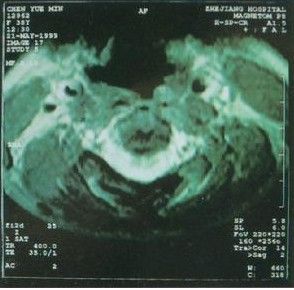

2.肥厚型心肌病普通胸片見左心室增大,但也可在正常範圍,晚期可有左房增大、肺淤血。主動脈不擴大,X線或核素心血管造影可顯示室間隔增厚,左心室腔縮小。核素心肌掃描可顯示心肌肥厚的部位和程度。